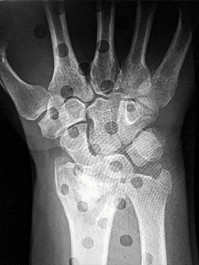

Question 6

A 22-year-old male falls onto an outstretched hand and sustains a displaced fracture through the proximal pole of the scaphoid. Avascular necrosis of the proximal pole is highly likely due to the disruption of its primary vascular supply. Which vessel provides this critical retrograde perfusion?

Explanation

The primary blood supply to the scaphoid is from the dorsal carpal branch of the radial artery, which enters the dorsal ridge of the scaphoid at the waist and courses proximally. This retrograde blood flow makes proximal pole fractures highly susceptible to avascular necrosis and nonunion. The superficial palmar branch provides a minor supply (about 20%) to the distal pole.